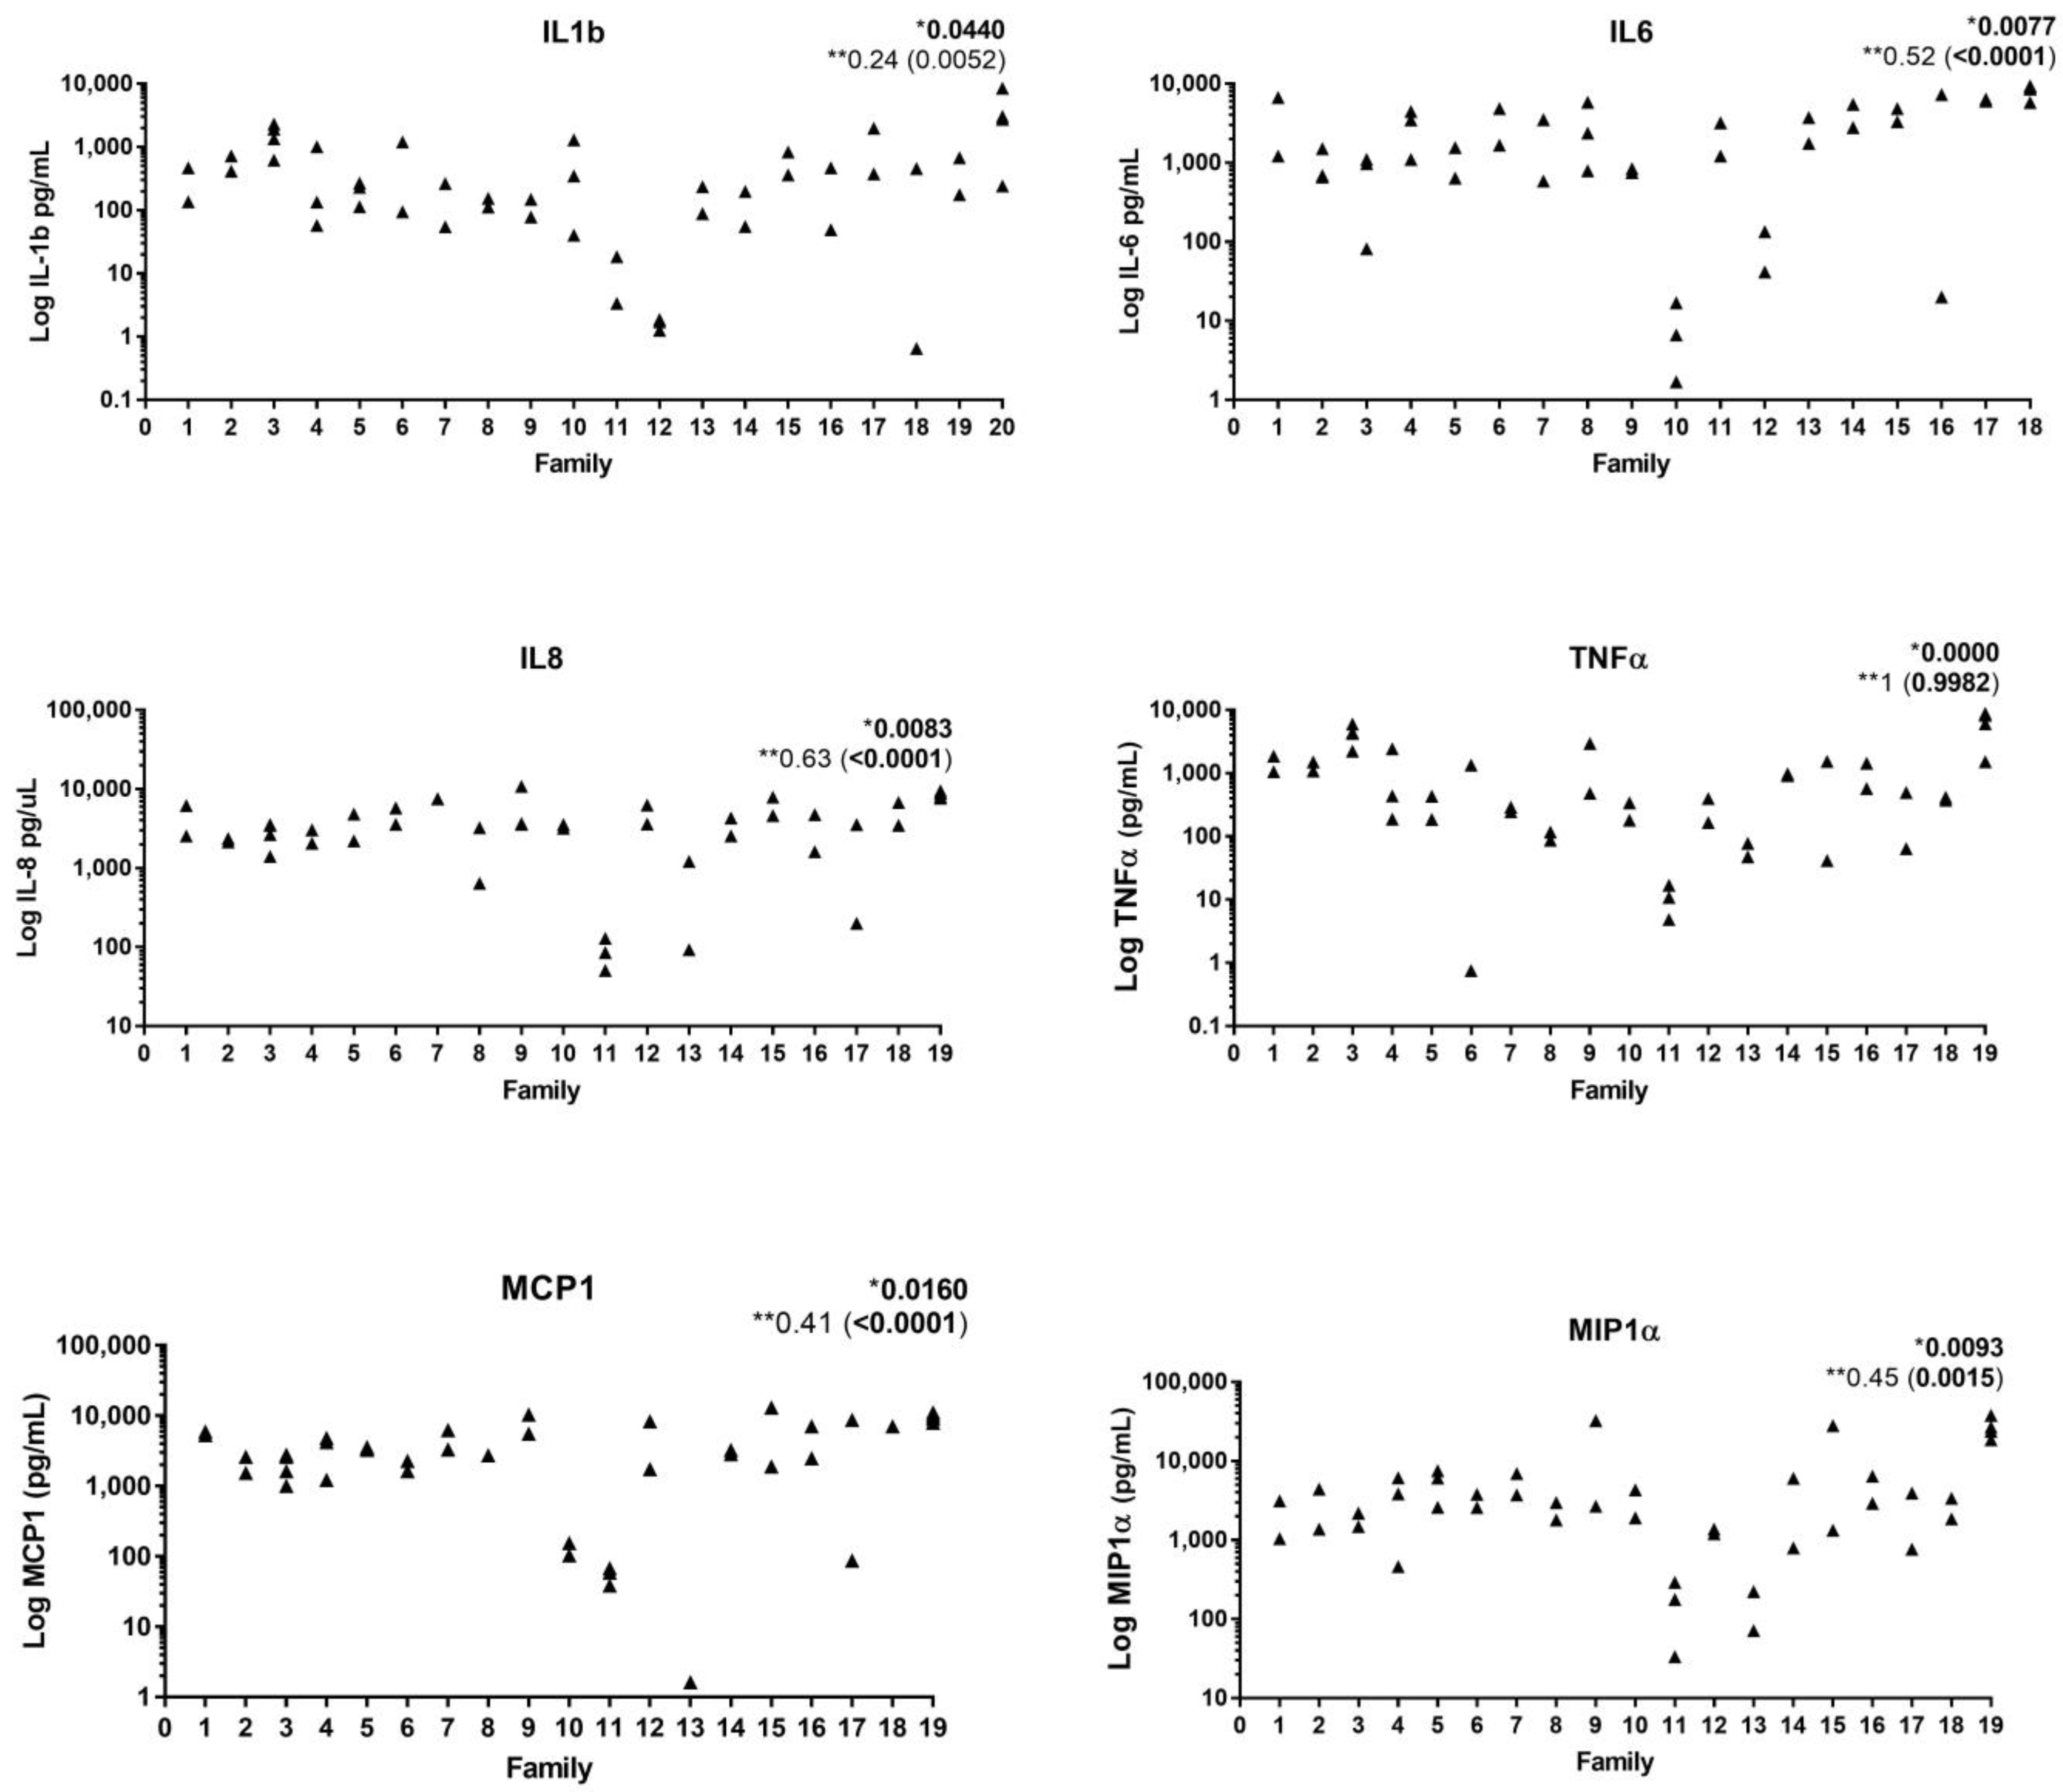

2. Immunological Aspects

- Branco-De-Almeida, L.S.; Cruz-Almeida, Y.; Gonzalez-Marrero, Y.; Huang, H.; Aukhil, I.; Harrison, P.; Wallet, S.M.; Shaddox, L.M. Local and Plasma Biomarker Profiles in Localized Aggressive Periodontitis. JDR Clin. Trans. Res. 2017, 2, 258–268. [Google Scholar] [CrossRef] [PubMed]

- Shaddox, L.M.; Wiedey, J.; Calderon, N.L.; Magnusson, I.; Bimstein, E.; Bidwell, J.A.; Zapert, E.F.; Aukhil, I.; Wallet, S.M. Local Inflammatory Markers and Systemic Endotoxin in Aggressive Periodontitis. J. Dent. Res. 2011, 90, 1140–1144. [Google Scholar] [CrossRef] [PubMed]

- Tabaa, M.; Adatowovor, R.; Shabila, A.; Morford, L.; Dawson, D.; Harrison, P.; Aukhil, I.; Huang, H.; Stromberg, A.; Goncalves, J.; et al. Pattern of Grade C Molar-Incisor Pattern Periodontitis in Families. J. Periodontol. 2023, 94, 811–822. [Google Scholar] [CrossRef]